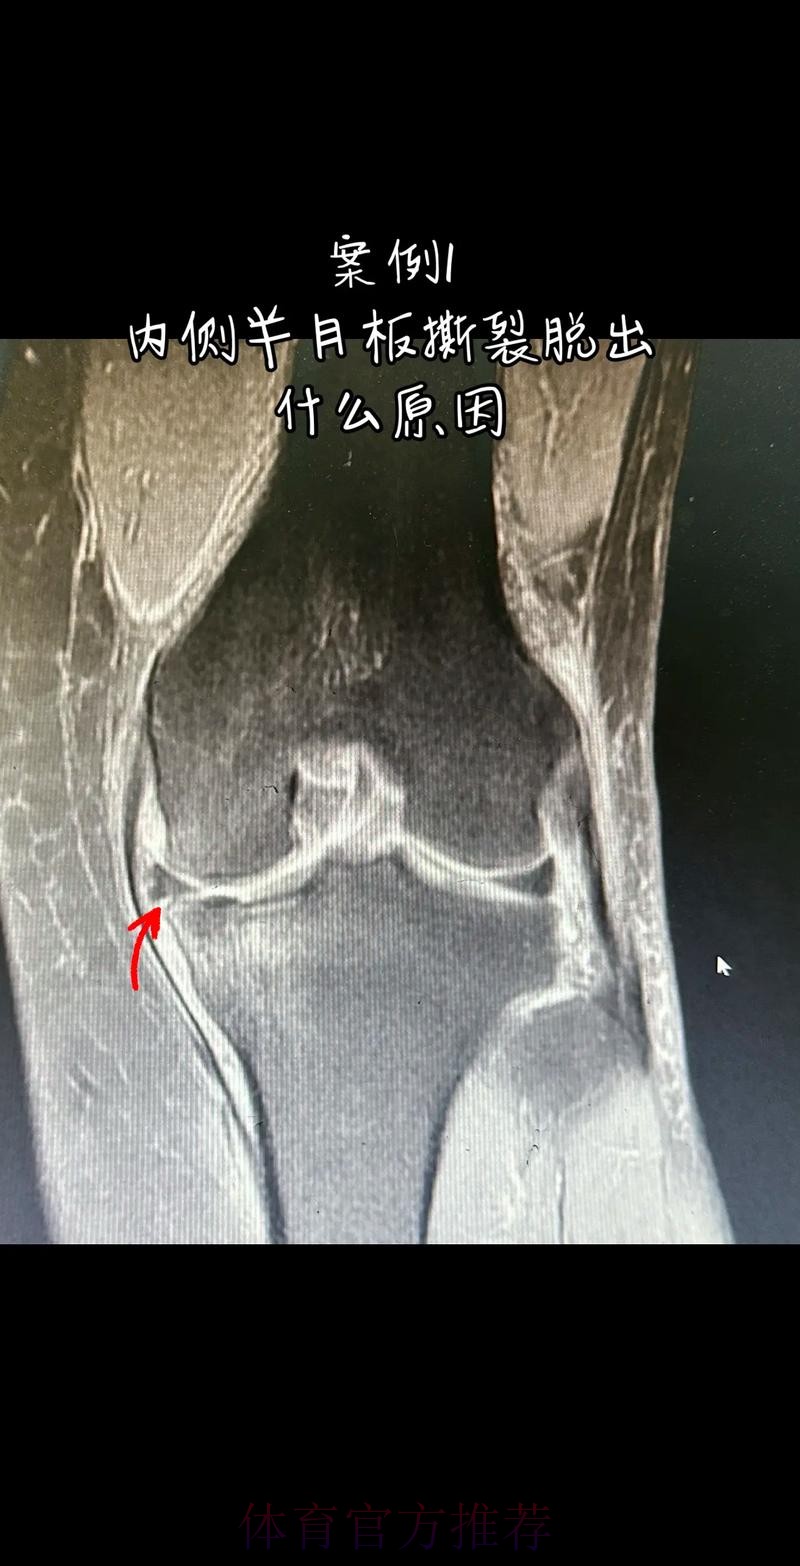

从医学角度看 半月板是膝关节内一块呈“C”形的软骨结构 其作用是缓冲冲击 稳定膝关节 并帮助分散压力 “左膝内侧半月板撕裂”通常说明在一次急停 旋转 或对抗中 半月板受到了超过其承受极限的力导致结构损伤 这类伤病常见于足球 篮球等需要频繁变向和对抗的项目 对于职业球员而言 半月板损伤严重程度不一 但共同点是都会影响支撑发力 跳跃以及变向时的稳定性 而官方给出的“预计伤缺6-8周”这个时间区间 往往对应的是中度损伤或通过微创手术加积极康复能够较快回归的情况 也意味着暂时没有出现必须长时间休战的最坏结果